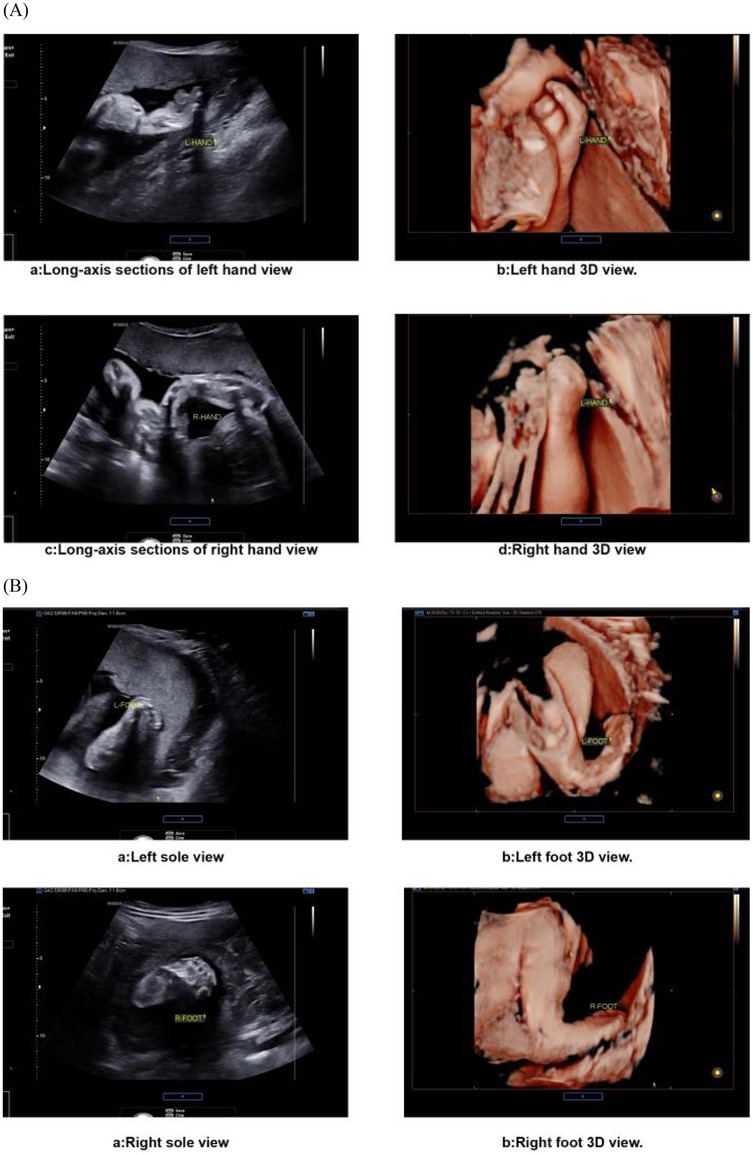

The prenatal assessment of syndactyly in Apert syndrome has evolved from static anatomical observation to dynamic functional evaluation (22). Traditional two-dimensional ultrasound primarily detects osseous fusion but exhibits limitations in visualizing cutaneous syndactyly due to technical constraints (23, 24). Advanced four-dimensional HDlive Flow imaging with spatiotemporal correlation overcomes these limitations by reconstructing perfusion patterns within fused digits (25). This technique discriminates Apert-specific “mitten hands” from other syndromic syndactylies by mapping unique vascular architectures, significantly improving diagnostic accuracy over conventional methods. Further refinement is achieved through reverse-mode rendering algorithms, which isolate osseous margins to reveal pathognomonic fourth metacarpal-phalangeal synostosis—a highly specific feature of Apert syndrome (26). Optimal visualization requires late-gestation imaging (>24 weeks), when digital ossification nears completion. Detection sensitivity progressively increases during this period, correlating with advancing skeletal maturation (27). Emerging artificial intelligence tools now automate digit segmentation, reducing operator-dependent variability in assessment (28, 29) (Figure 3).

(A) Ultrasound images showing fetal hands: two-dimensional long-axis section of the left hand and its 3D view; right hand in similar formats. (B) Images of fetal feet: 2D sole views and 3D representations of both left and right feet.

Figure 3. Ultrasound images of fetal extremities in apert syndrome. (A) The presence of an abnormal hand shape, a fixed posture, and an atypical arrangement of the metacarpal bones and phalanges is indicative of the “glove sign”. (B) The feet display a “glove sign”.